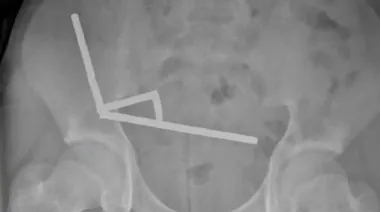

13-летнему мальчику в Новой Зеландии хирурги удалили часть кишечника после того, как он проглотил почти 200 неодимовых магнитов. Эти магниты в 50 раз мощных обычных и представляют большую угрозу для здоровья.